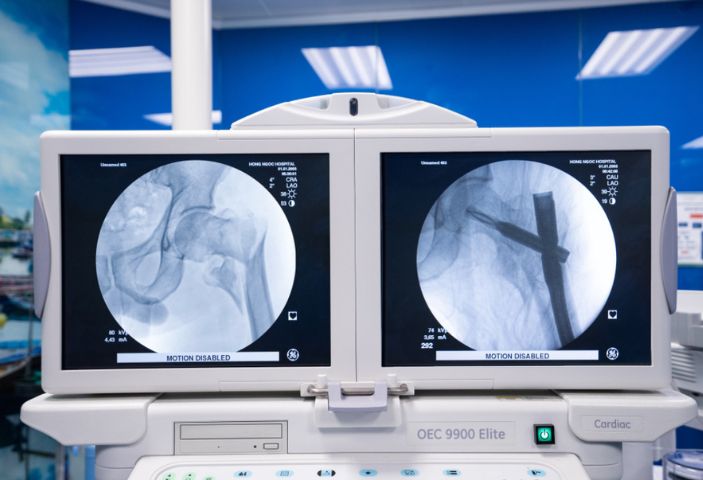

- Cố định trong hay Kết hợp xương sinh học

Phẫu thuật để sắp xếp lại xương từ bên trong và sau đó cố định bằng ốc vít hoặc mảnh kim loại. Phù hợp cho trường hợp gãy xương phức tạp, đảm bảo ổn định và tái tạo xương chính xác.

+ Đường mổ nhỏ chỉ từ 0.5 – 3cm cho sẹo nhỏ thẩm mỹ, ít xâm lấn mô mềm, ít gây mất máu, bảo tồn được các mạch máu nuôi ổ gãy, hạn chế tối đa nhiễm trùng.

+ Sử dụng đinh, nẹp vít chất liệu an toàn, tương thích với cơ thể, cung cấp độ vững khi vận động, kích thích hình thành tế bào xương và tế bào sụn cùng các sợi collagen, giúp xương liền tự nhiên, hồi phục vận động sau 1 ngày phẫu thuật.

+ Kết hợp thiết bị y tế hiện đại: bàn mổ chỉnh hình, máy C-arm,… xác định chính xác vị trí gãy, nắn xương về đúng vị trí, tránh biến chứng sau phẫu thuật.

Kết hợp xương sinh học - Vận động sau 1 ngày phẫu thuật